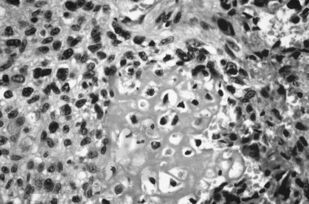

В книге представлены возможности морфологических исследований (патолого-анатомических и цитологических) в определении морфофункционального состояния клеток и тканей двух типов первичных злокачественных новообразований костей до проведения, в динамике и после завершения курса лучевой терапии. Показана значимость использования полученных данных в выборе метода лечения, в т. ч. и лучевого, в оценке прогноза и эффективности лучевой терапии при злокачественных новообразованиях костей.